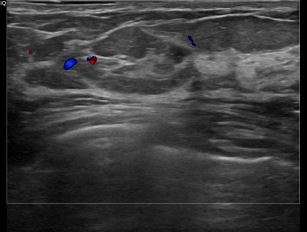

상기환자는 양성추정관찰 하시는 50대 중반

여성분으로 의심스러운 우측유방혹 조직검사 시행해 점액성암으로 진단되었습니다